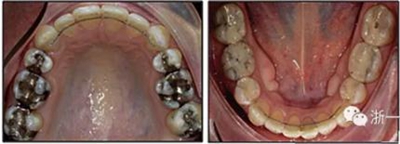

患者曾行正畸治療,現覺笑容不美觀前來就診?;颊哒嬗^及側貌示下頜發(fā)育不足,偏高角,唇閉合不全。上下頜中線齊。覆合、覆蓋4毫米。磨牙關系及尖牙關系II類。上頜擁擠度4mm,下頜擁擠度6mm。4顆第一前磨牙在第一次正畸治療時已拔除。上下牙弓呈尖圓型,牙弓狹窄。

治療結果:

患者側貌改善,下唇唇肌緊張消失,上下唇可自然閉合。磨牙及尖牙關系糾正至I類,覆合覆蓋正常。上下頜弓型糾正至卵圓形,牙弓寬度增加。頭影測量分析示SNA角81.8°,ANB角3°。頭影測量重疊圖示下頜骨向后旋轉,垂直面高度略有增加。